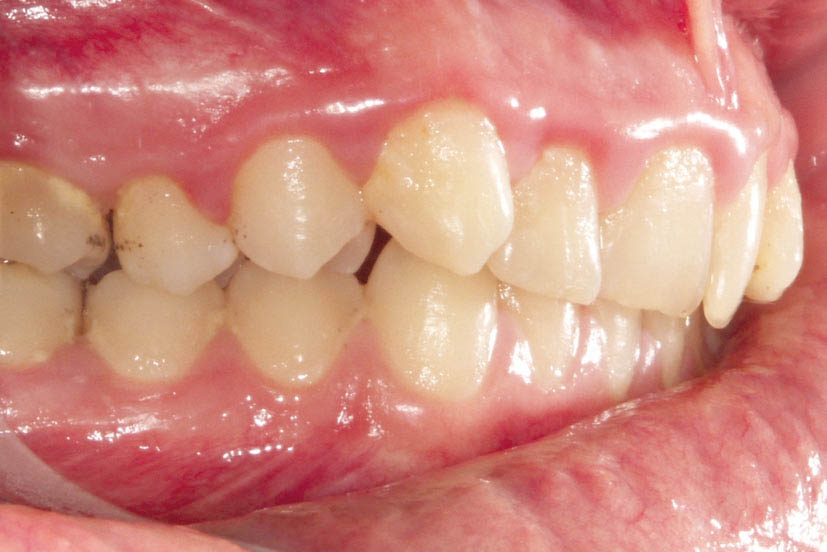

شکل 20-2: نرسیدن به اورجت نرمال در انتهای درمان

بعضی مواقع وقتی به انتهای درمان میرسید و کانینهای بالا به پشت کانینهای پائین میرسند (رابطه کلاسI کانینی) ولی اورجت بیمار نرمال نمیشود (شکل 20-2).